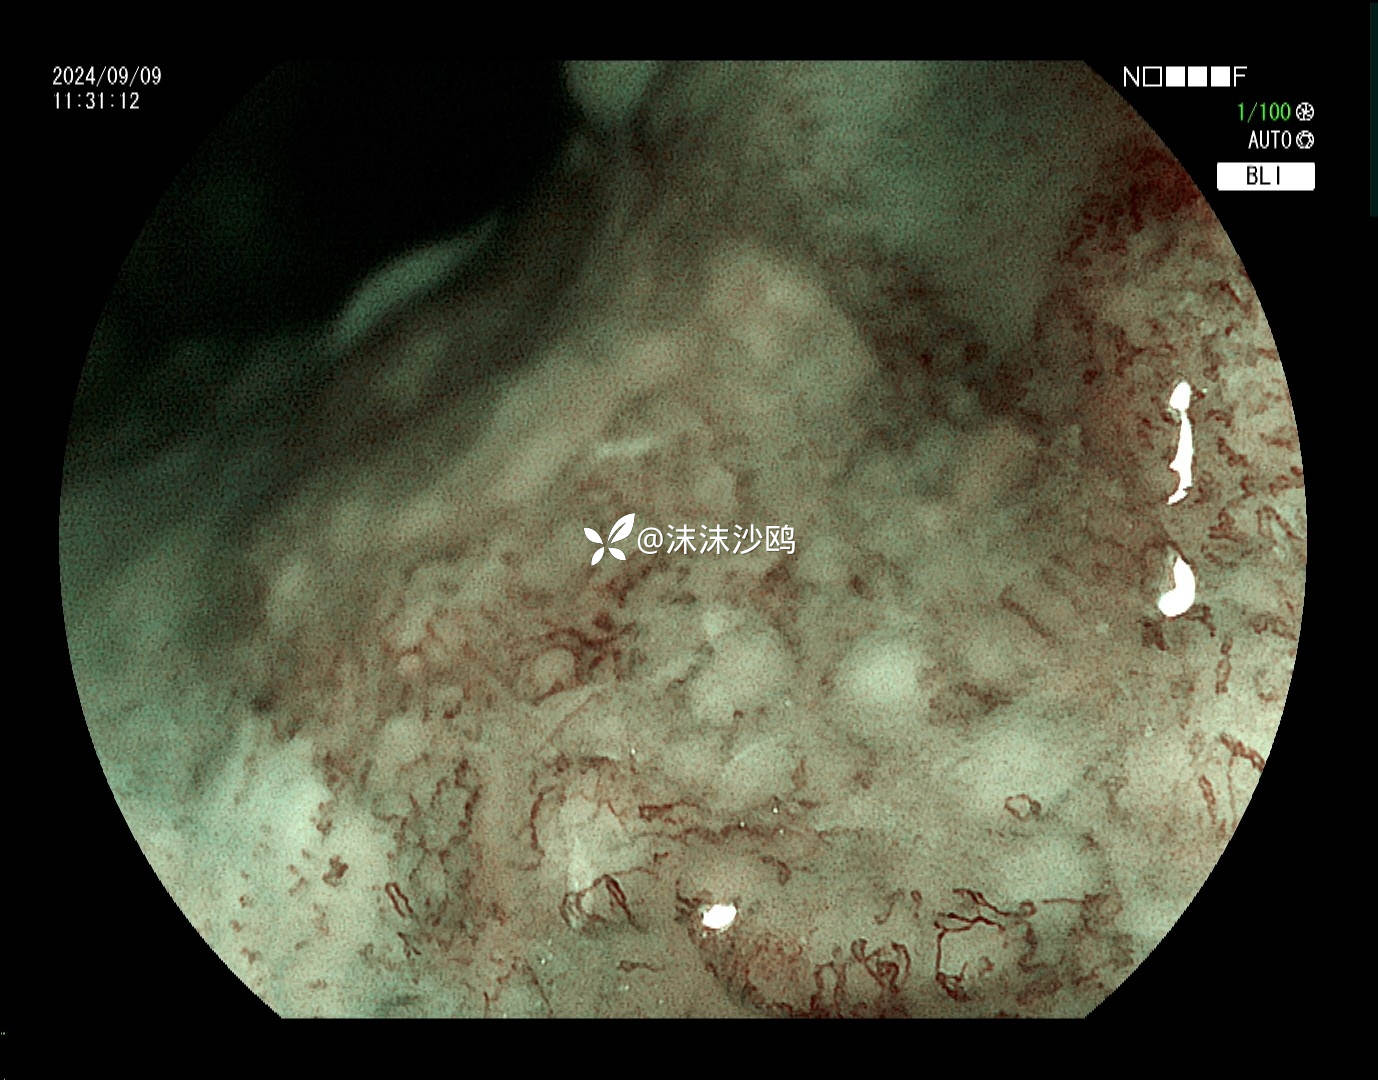

ME

该患者平素无明显症状,吸气注气观察病灶延展性,柔软度可,白光观察粘膜呈现发红粗糙,BLI放大观察呈现明显茶褐色,可见B1型血管,局灶可见紊乱生长的B2型血管,并见AVA区域,感觉小于0.5mm。镜下考虑浸润深度,不超过SM1,应该有内镜下D的可能性。等病理结果,希望符合内镜诊断。